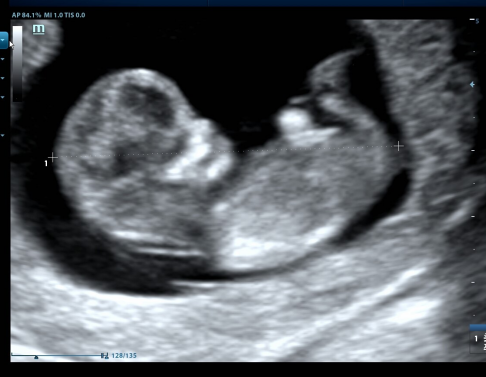

首先说说超声医师是怎么判断胎儿性别的。

判断性别主要是二维扫查时观察外生殖器,从而判断是男孩儿还是女孩儿。

但这也不是百分百的。

因为容易受脐带、手指、伪像等等原因,导致“看花眼”,误判。

但,报告会配有几张检查图像。

图像一般都是重点观察部位。

头、股骨、心率等。

但保不齐有时选图时选错,明明想选个腿,没想到把腿旁边的器官也选进去了。。。(超声医师看到了,以后选图要注意哦。。。)

所以上述也只是阐述一种可能:报告是不会描述性别,但图像有可能会暴露性别。